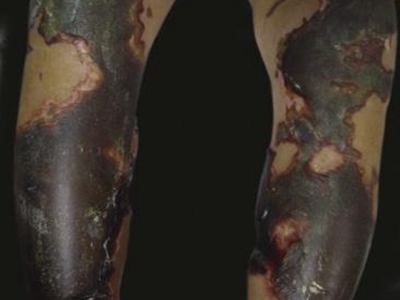

腿

焦痂

暴发性紫癜双腿皮肤大面积焦痂图

暴发性紫癜表现为皮肤坏死,失去知觉,坏死始于双腿,并向近端延伸,出现大疱,最终形成坚硬的焦痂,皮肤大面积变黑,像烧焦了一样。